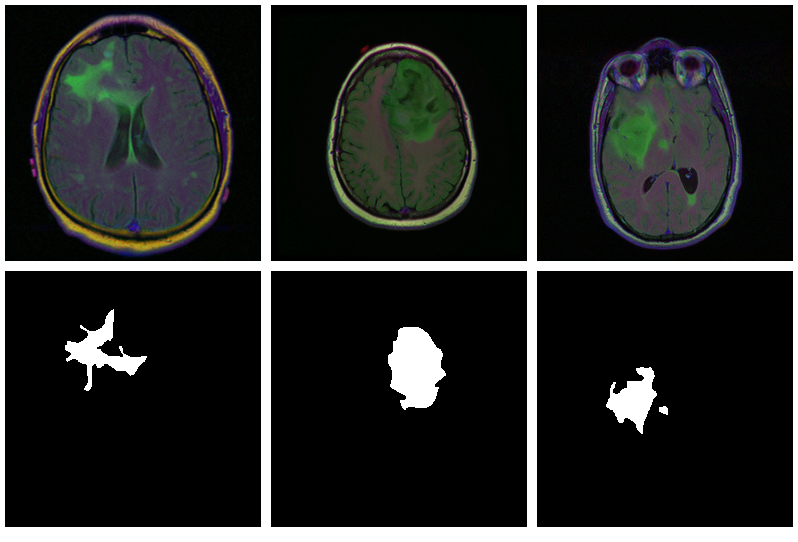

Now, since we don’t have a separate test set, we already know the average out-of-sample metrics; but in the end, what we care about are the generated masks. Let’s view some, displaying ground truth and MRI scans for comparison.

1

We also print the individual cross entropy and dice losses; relating those to the generated masks might yield useful information for model tuning.

Sample 1, bce: 0.088406, dice: 0.387786}

Sample 2, bce: 0.026839, dice: 0.205724

Sample 3, bce: 0.042575, dice: 0.187884

Sample 4, bce: 0.094989, dice: 0.273895

Sample 5, bce: 0.026839, dice: 0.205724

Sample 6, bce: 0.020917, dice: 0.139484

Sample 7, bce: 0.094989, dice: 0.273895

Sample 8, bce: 2.310956, dice: 0.999824

While far from perfect, most of these masks aren’t that bad – a nice result given the small dataset!